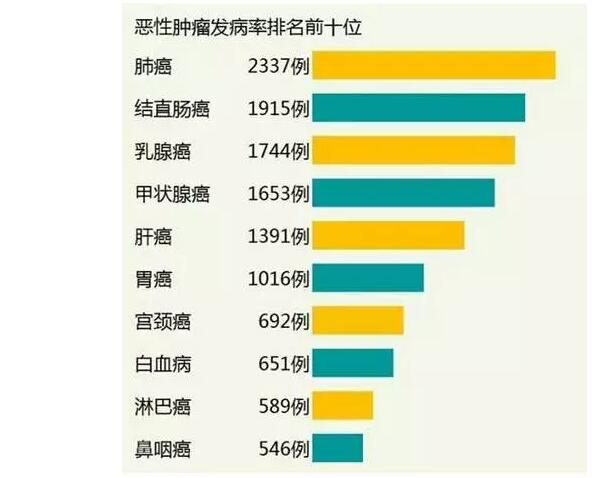

������ע����������Ӧ�ö�֪�����ڹ�ȥ��ʮ����ҹ���ֱ����(��ƴ�)���в�ѧ�������ڷ����仯�������������������ʵĵڶ�λ��Ů�����������ʵĵ���λ�����ҳʸ߷�������λ�������ữ��չ����Ҳ�ѳ�Ϊ�����ݡ��ĵڶ���֢��������ԼΪʮ���֮��ʮ����10��ǰ��ȣ��������ȳ���50%���ﵽ�˷������ˮƽ������˿��£������йش�ɸ������ĺô������ж�����֪�����ֶ�֪��������?���ھ�����������һ��һ����Ϊ���ڴ�ɸ������ô�����ʵ����!

����Ϊ�˽��ʹ��������Ӱ�죬���ݶ���س�ҽԺ����������С��̽��8�������ͳ������ˣ�ͻ�ƴ�ͳ�ĸس����ä����120°��ⲻ�����ǣ�5���ӾͿ���ȷ�ﲡ�飬������ֹ������Ϯ!